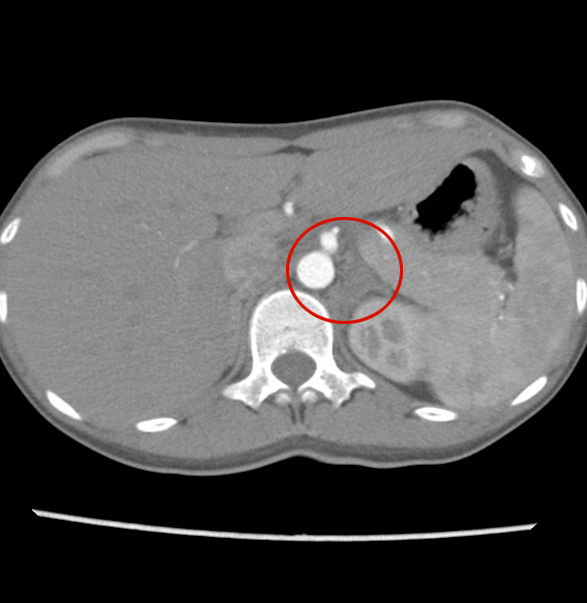

- 【1週間後 単純CT】

-

- 右副腎の腫大

- 右副腎周囲の脂肪織濃度上昇

- 左副腎の腫大は軽減